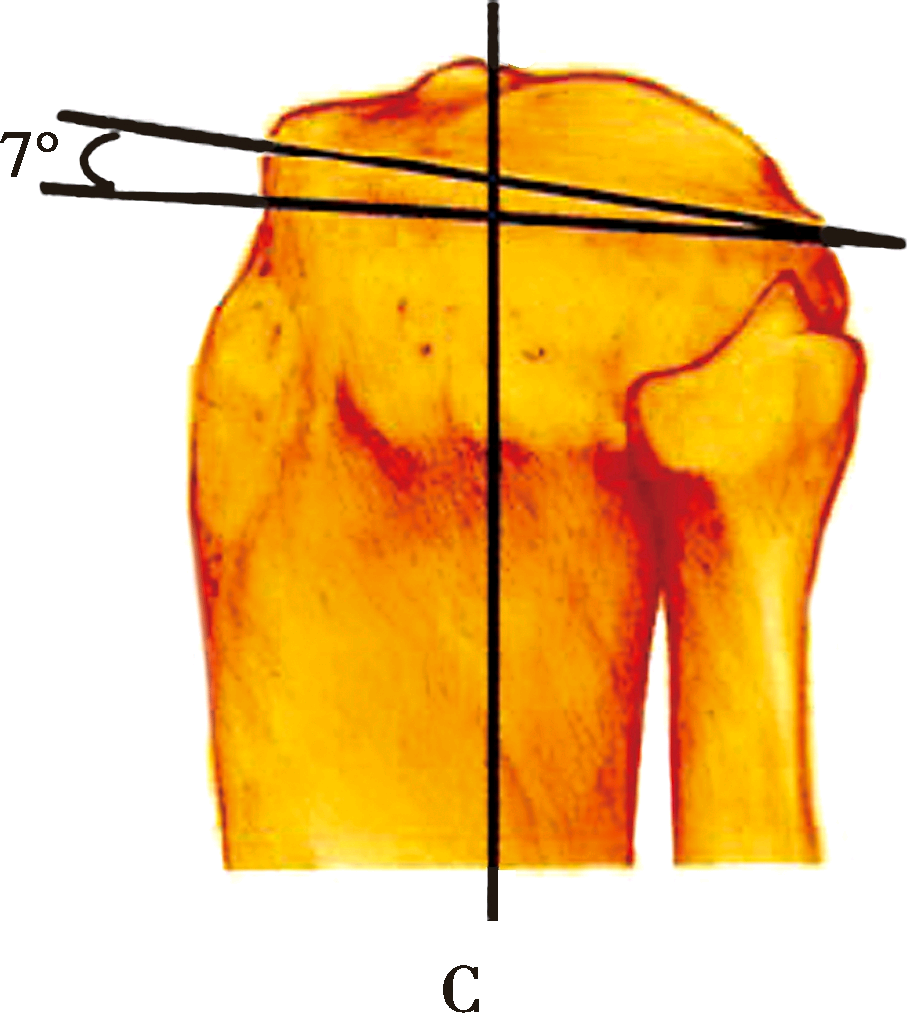

下肢矢状面对线上

A下肢的力线:经过股骨头中心和踝关节中心的连线,该线经过膝关节中心

B胫骨关节面内侧后倾平均约12°

C外侧关节面后倾平均约7°

在矢状面上,下肢的力线是经过股骨头中心和踝关节中心的连线,该线经过膝关节中心。胫骨关节面与力线有平均10°的后倾,由于胫骨平台关节面内外侧后倾角度不同,内侧后倾平均约12°,外侧关节面后倾平均约7°